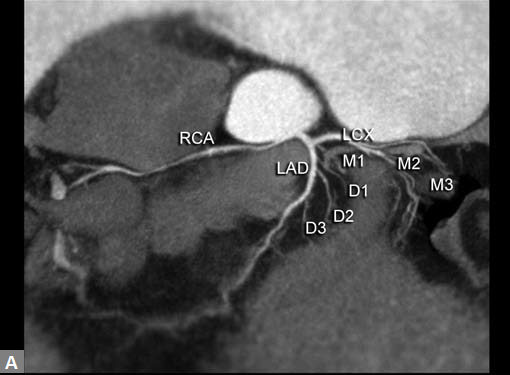

Coronary stenosis (Fig. 4) can be detected efectively.

Degree of stenosis is categorized as minimal, mild, moderate

and marked. Diagnostic accuracy falls as one goes down

to distal part of vessel as caliber decreases. Ostial stenosis

LM and right coronary artery (RCA) can be picked. Rarely

detection of ostial lesion may be the sole purpose of CT, after

an inadequate evaluation of ostia on catheter angiogram.

Even in CT, evaluation of ostial lesion is hard as compared

to diagnosis of segmental stenosis.